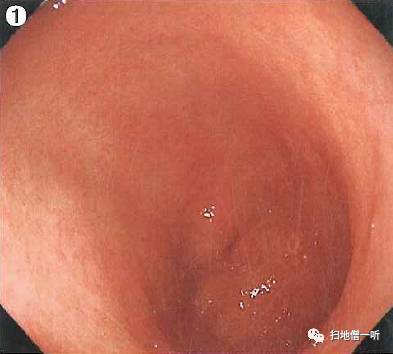

A:胃癌在图2。HP未感染胃癌。

整体胃粘膜光滑,未见明确萎缩。白光下可见无数小红点规则排列(RAC),所见为HP未感染征像。

接近观察及NBI非放大观察可见粘膜呈退色调改变,靛胭脂染色后界限不清。未分化癌初期可呈IIb表现,随着肿瘤进展可出现凹陷。本院数据显示当肿瘤小于10mm时 IIb36%,IIc64%;肿瘤11mm-20mm时 IIb6%,IIc94%

小结:RAC提示HP阴性

HP阴性需要注意寻找未分化癌

未分化癌以退色调多见

初期未分化癌可只出现色调变化而不伴随凸凹变化